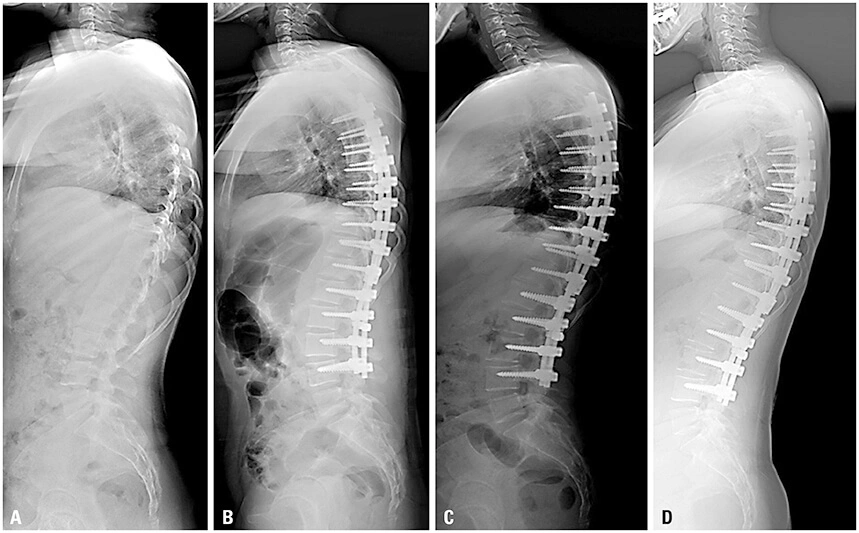

- Abnormal spinal curves

While X-rays excel in pinpointing fractures and skeletal defects, they also aid in identifying connective tissue problems. Typically, these imaging studies confirm symptoms and examination findings to pinpoint the source of pain, particularly in cases of direct trauma to the back, back pain accompanied by fever, or weakness and numbness in the limbs.

X-ray Imaging of Spinal Bones Dense tissues characterized by a high calcium content, such as bones, exhibit reduced X-ray absorption, resulting in a white-colored representation on the photographic film. Bones emerge as the most distinct and clearly visible structures in X-ray images. The architecture, form, and alignment of spinal vertebrae and facet joints can be precisely documented through spinal X-rays.